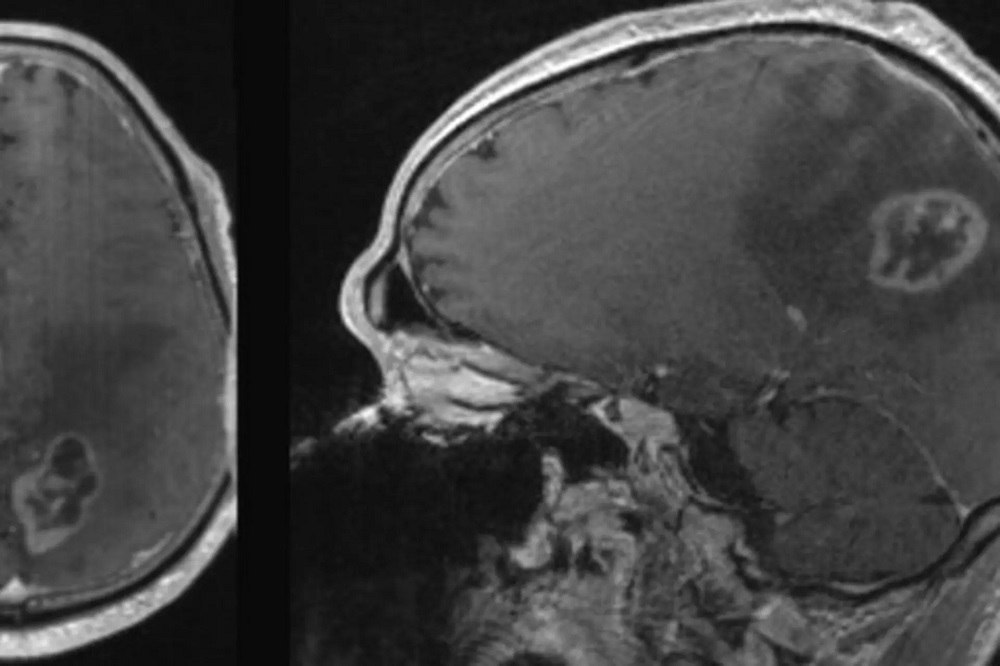

بڕیارە لە ئایندەیەکی نزیکدا بەردی بناغە بۆ دروستکردنی نەخۆشخانەیەک دابنرێت و بەڕێوەبەری گشتیی تەندروستیی دھۆکیش دەڵێت، بۆ یەکەم جارە نەخۆشخانەیەکی لەو شێوەیە لەسەر ئاستی عێراق دەکرێتەوە.

د. ئەفراسیا مووسا، بەڕێوبەری گشتی تەندرووستی دھۆک، ڕایگەیاند: "لە داهاتوویەکی نزیکدا بەردی بناغەی درووستکردنی نەخۆشخانەیەک بۆ چاندنی مێشک و شێرپەنجەی خوێن لە شاری دھۆک دادەنرێت، نزیکەی حەوت ملیار دینار عێراقی بۆ درووستکردنی تەرخان کراوە، نەخۆشخانەکە دەکەوێتە پشت نەخۆشخانەی ھیڤی لە سەنتەری شاری دھۆک."

د. ئەفراسیا مووسا ئاماژەی بۆ ئەوە کرد: "نەخۆشخانەکە کاریگەری خۆی دەبێت، چوونکە لەسەر ئاستی عێراق بۆ جاری یەکەمە نەخۆشخانەیەک بۆ چاندنی ئێسکی مێشک دەکرێتەوە، پێشتر نەخۆشخانەی وا نەبووە لەسەر ئاستی عێراق و کوردستان، لەبەر ئەوە کردنەوەی نەخۆشخانەیەکی وەھا گرینگ ھەنگاوێکی دیکەیە بۆ خزمەتکردنی ھاووڵاتییانی کوردستان و بەتایبەتی پارێزگای دھۆک."